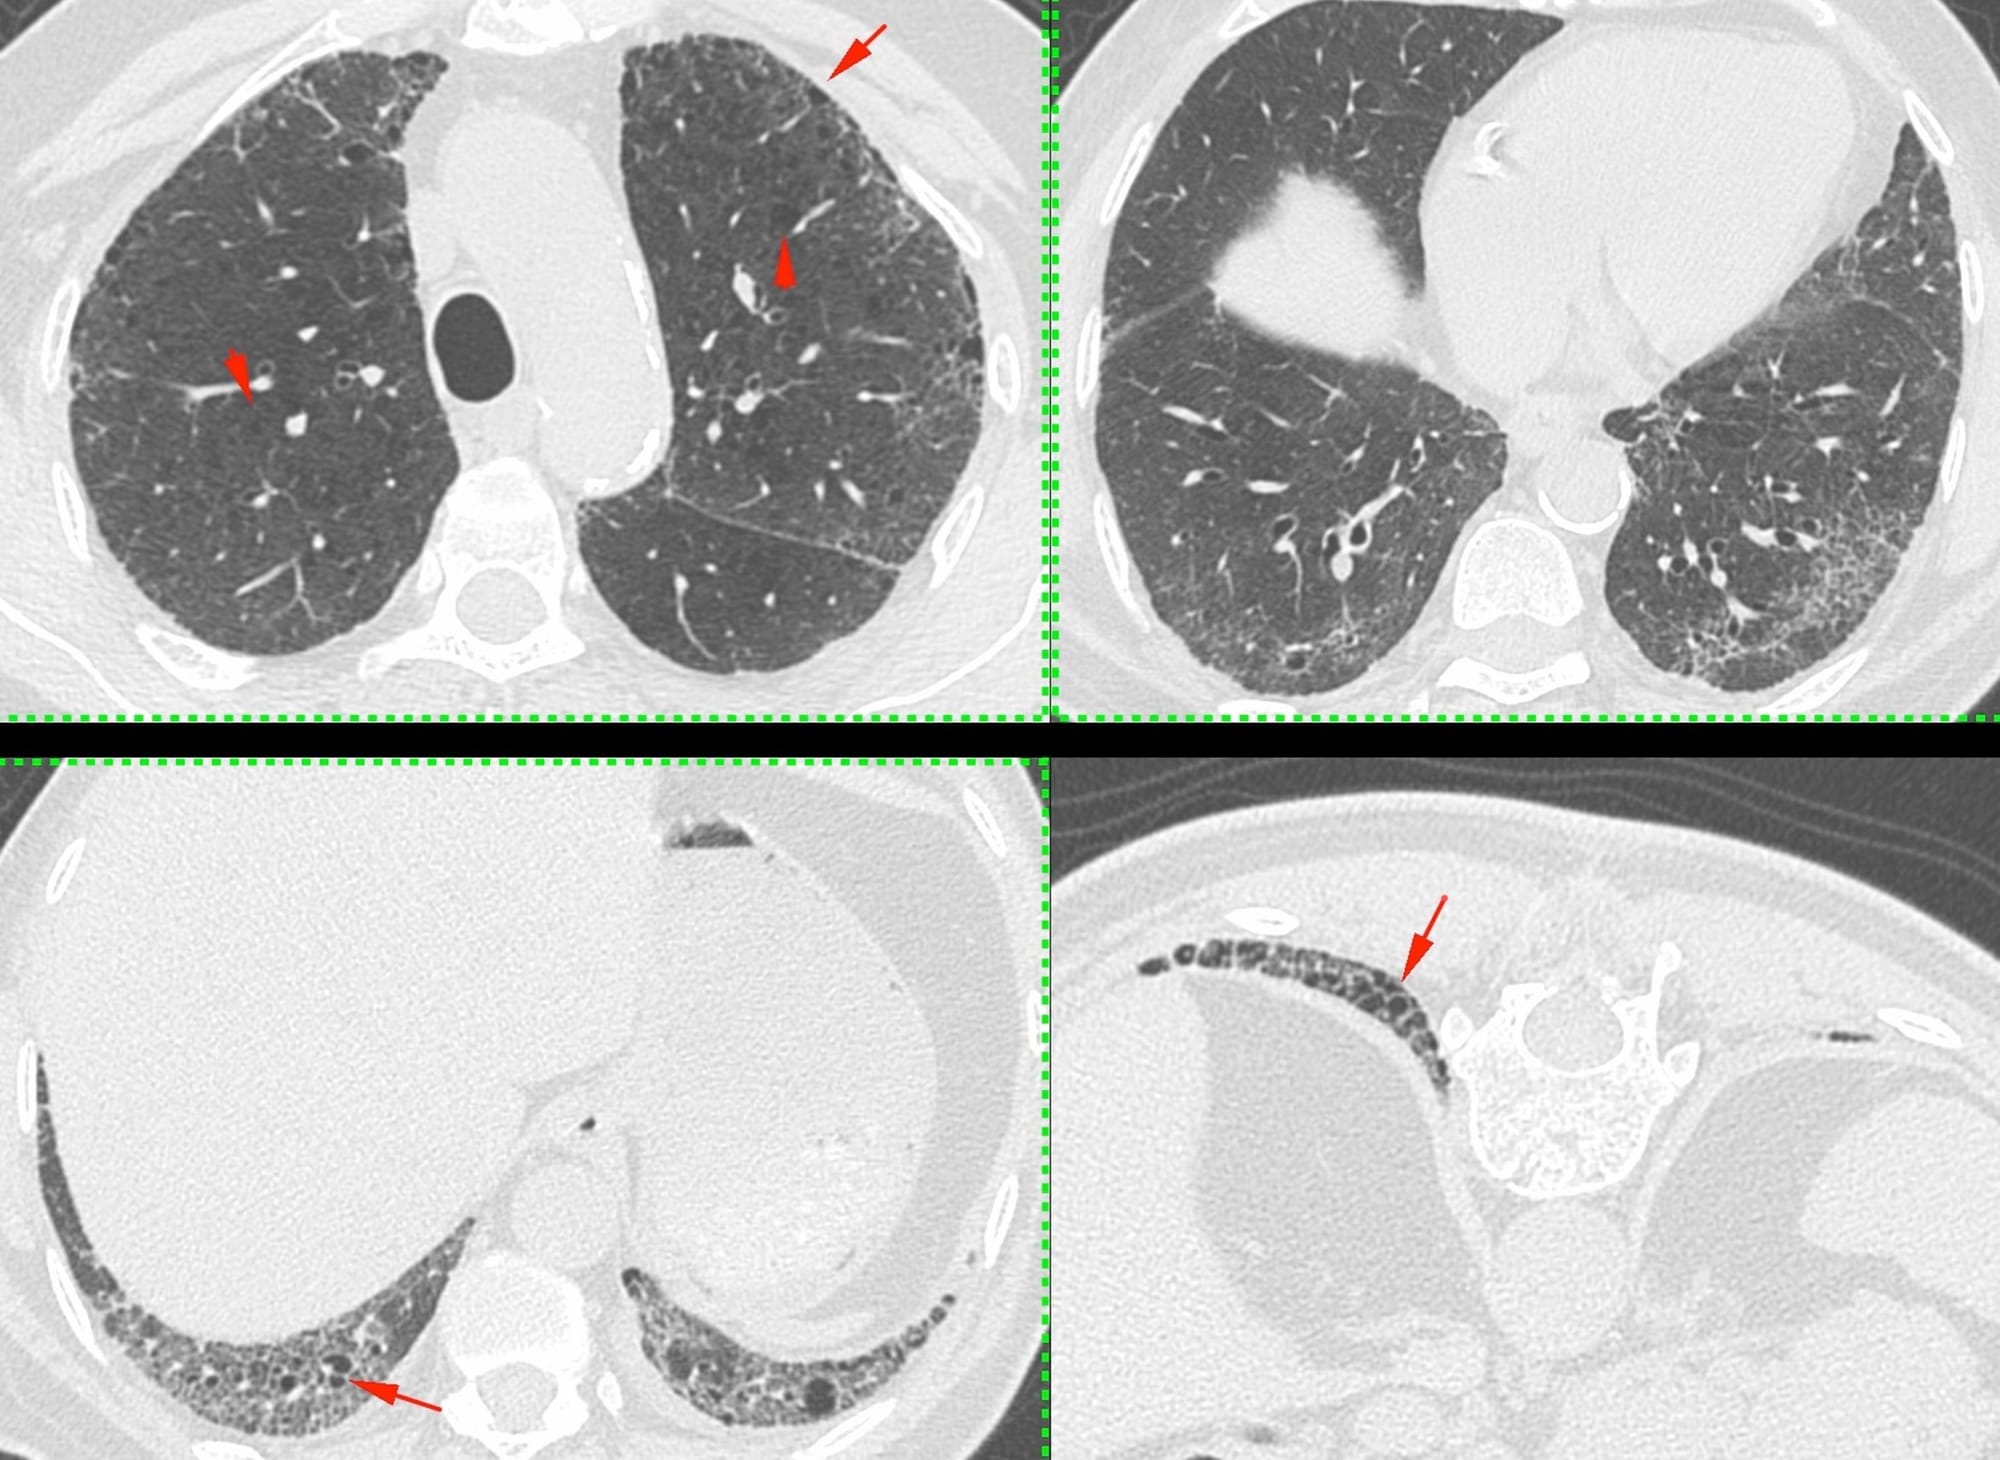

A 69-years old ex-smoker presented with breathlessness in 2020.

He had UIP/IPF.

He progressed over the next 3 years.

One day in 2024, he presented with acute increased dyspnea.

Thoughts?

- Acute exacerbation

- Acute infection

- Pulmonary edema/cardiac failure?